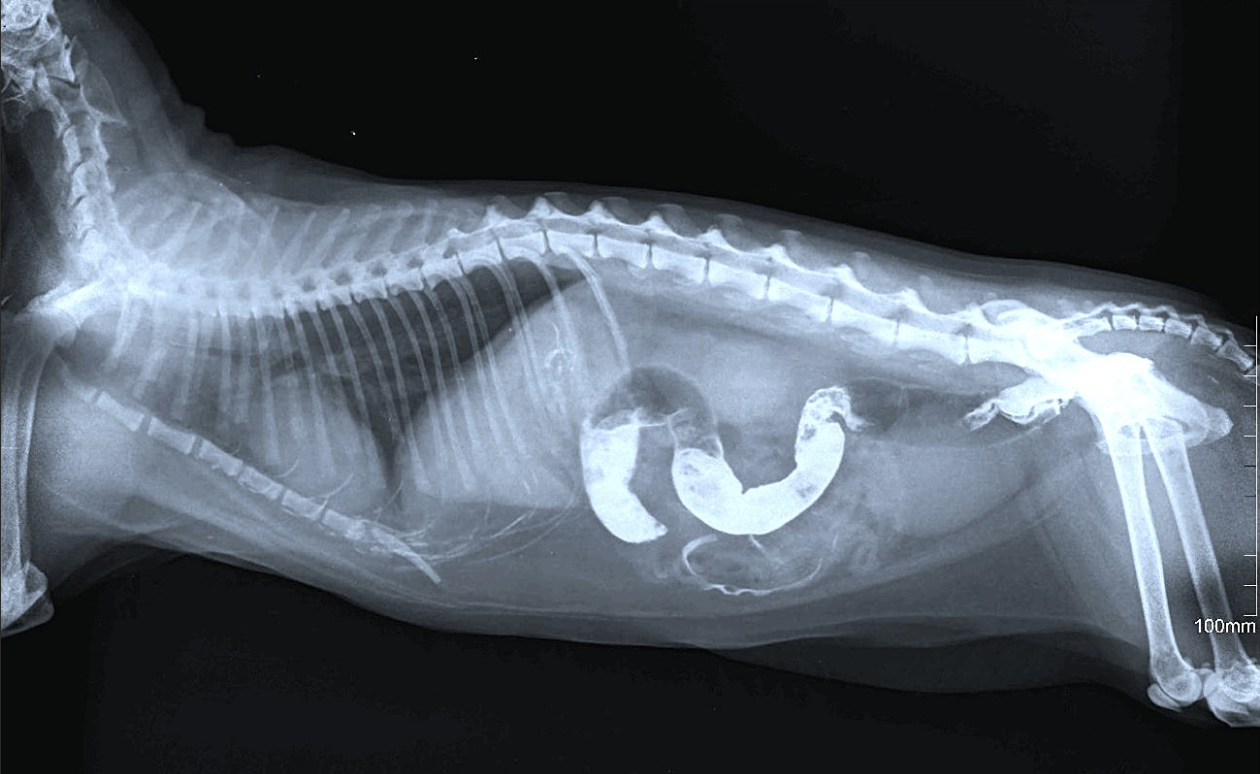

Причину заболевания устанавливают при клиническом осмотре, собирают анамнез. Проводят рентгенологические исследования с контрастным веществом. В сомнительных ситуациях применяют методы диагностической лапаротомии. Исключают запоры, при которых наблюдают сходные патологические симптомы.

Самым показательным обследованием является в данном случае рентген брюшной полости, особенно с применением контрастного вещества, например, сернокислого бария.

- рентгенологическое исследование кишечника обязательно при постановке данного диагноза. При введении рентгеноконтрастного вещества в просвет кишечника можно определить уровень развития кишечной непроходимости;